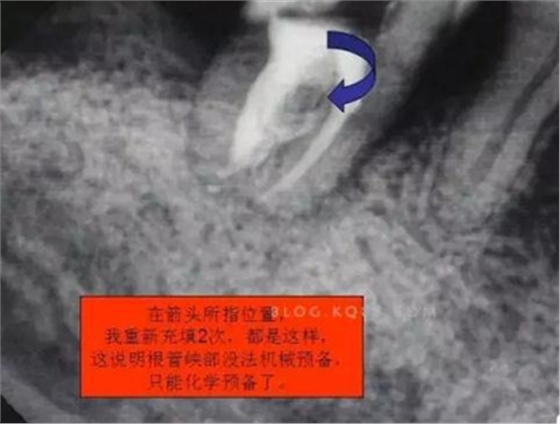

圖五

根管預(yù)備后可以確定這個是C型根管了。

6.本病例,由于連接近遠(yuǎn)中2個根管的融合區(qū)頰舌徑過于狹窄,在x線片上顯示不清,而唯一能表現(xiàn)的是近遠(yuǎn)中分離的2個獨(dú)立的根管,將K銼放置到頰側(cè)根管內(nèi),有時在x線片上表現(xiàn)出根分叉處可能穿孔,這也是C型根管在x線上的重要特征。